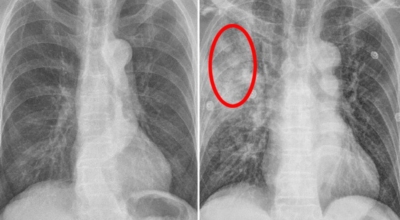

폐암 검사는 X-ray를 통해서 검사하는데 , 크기가 작거나 구석에 위치한 경우 확인이 어려운 경우도 있습니다. 그리고 조직 검사를 통해서 정확한 진단을 하게 돼요. 폐암이 발견되면 종양의 크기나 전이 여부 , 위치에 따라서 수술 여부를 결정하게 돼요.